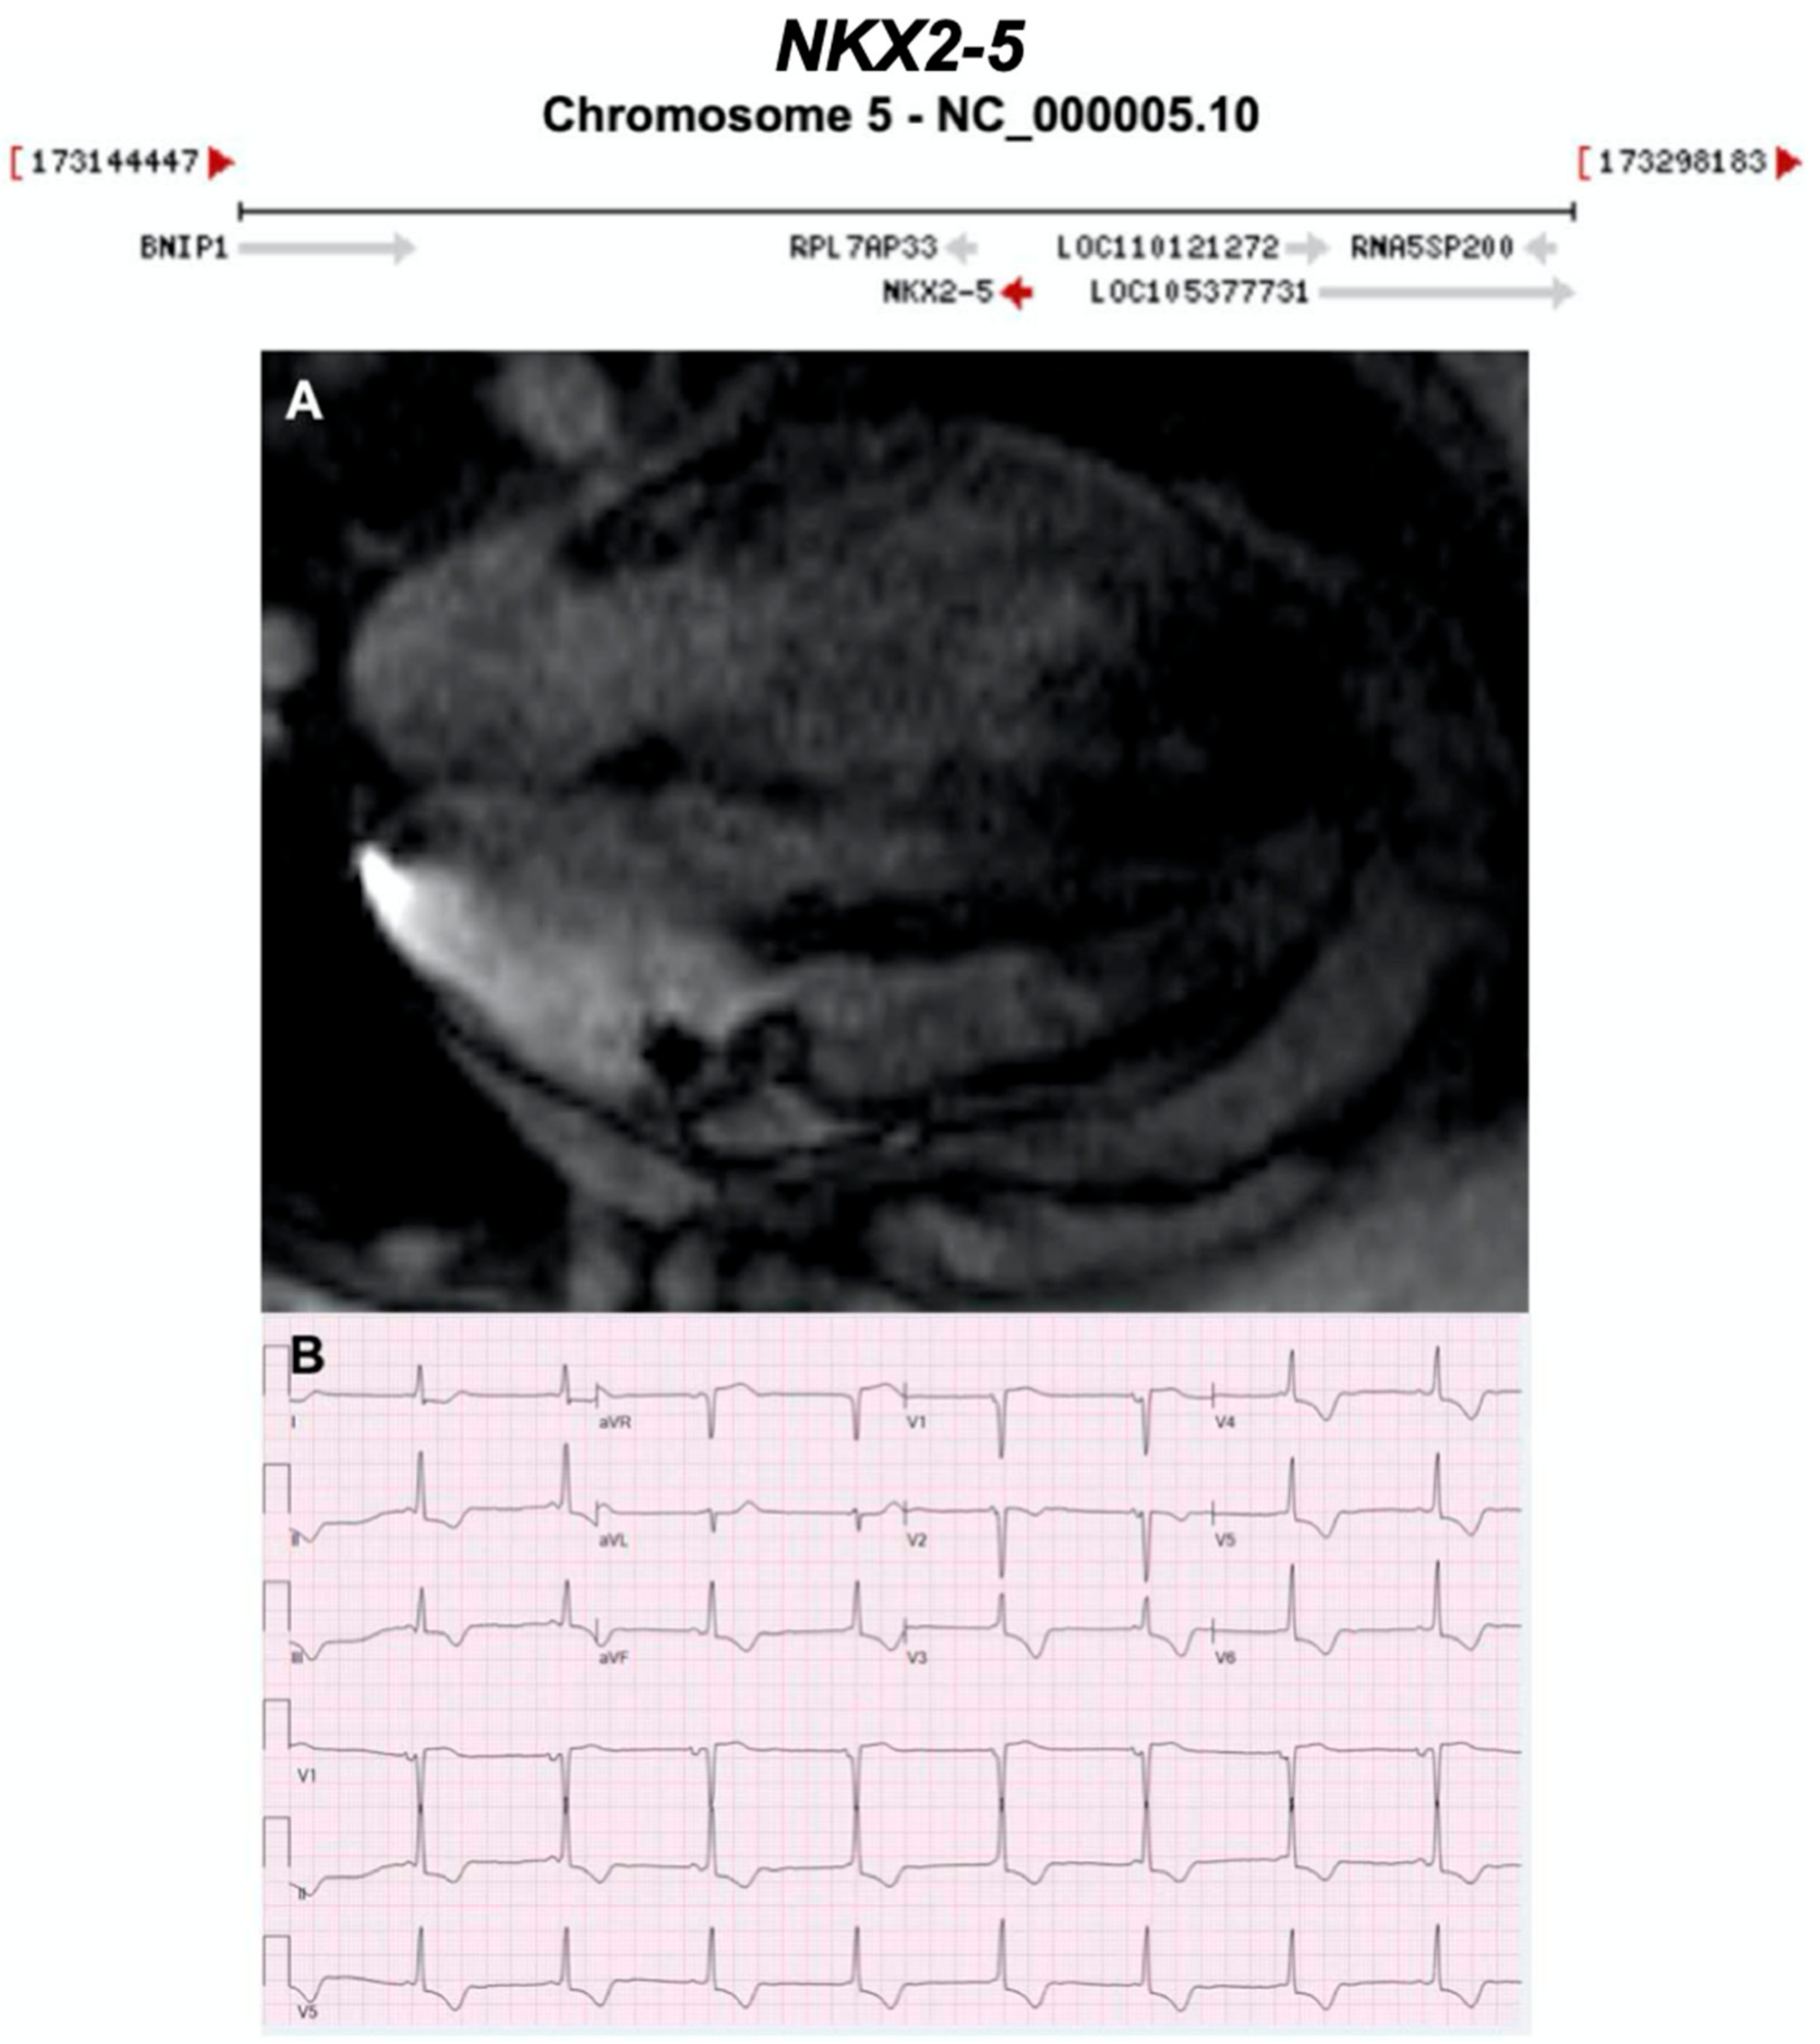

3.2.15. NK2 Homeobox 5 (NKX2-5) (Encoded by NKX2-5)

- Reamon-Buettner, S.M.; Borlak, J. NKX2-5: An update on this hypermutable homeodomain protein and its role in human congenital heart disease (CHD). Hum. Mutat. 2010, 31, 1185–1194. [Google Scholar] [CrossRef] [PubMed]

- Yuan, F.; Qiu, X.B.; Li, R.G.; Qu, X.K.; Wang, J.; Xu, Y.J.; Liu, X.; Fang, W.Y.; Yang, Y.Q.; Liao, D.N. A novel NKX2-5 loss-of-function mutation predisposes to familial dilated cardiomyopathy and arrhythmias. Int. J. Mol. Med. 2015, 35, 478–486. [Google Scholar] [CrossRef] [PubMed]

- Perera, J.L.; Johnson, N.M.; Judge, D.P.; Crosson, J.E. Novel and highly lethal NKX2.5 missense mutation in a family with sudden death and ventricular arrhythmia. Pediatric Cardiol. 2014, 35, 1206–1212. [Google Scholar] [CrossRef] [PubMed]

- Sveinbjornsson, G.; Olafsdottir, E.F.; Thorolfsdottir, R.B.; Davidsson, O.B.; Helgadottir, A.; Jonasdottir, A.; Jonasdottir, A.; Bjornsson, E.; Jensson, B.O.; Arnadottir, G.A.; et al. Variants in NKX2-5 and FLNC cause dilated cardiomyopathy and sudden cardiac death. Circ. Genom. Precis. Med. 2018, 11, e002151. [Google Scholar] [CrossRef]

| NKX2-5 | Homeobox | Unknown | AD | - | 5q35.1; 3 | - |